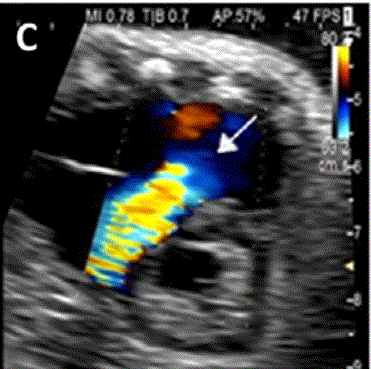

图27进展性主动脉狭窄。一例23周胎儿的严重主动脉狭窄,伴有扩张和低动力性左心室(LV)伴心内膜弹性纤维变性。(A) 彩色多普勒显示,主动脉瓣(箭头)开始出现花彩血流(左),频谱多普勒显示阶差为 25 毫米汞柱(右(B) 二尖瓣(MV)流入是单相的,持续时间短(左),二尖瓣反流提示左心室收缩压高(46毫米汞柱压力梯度加左心房压力;右图)。(C)存在逆行主动脉弓流(红色,左)和左至右心房流(红色、右)是预测由于通过左心的流量减少而在妊娠期间发展的进行性左心发育不全的额外发现。(D)LV逐渐变为球状,长度缩短,到36周时不再形成心尖。